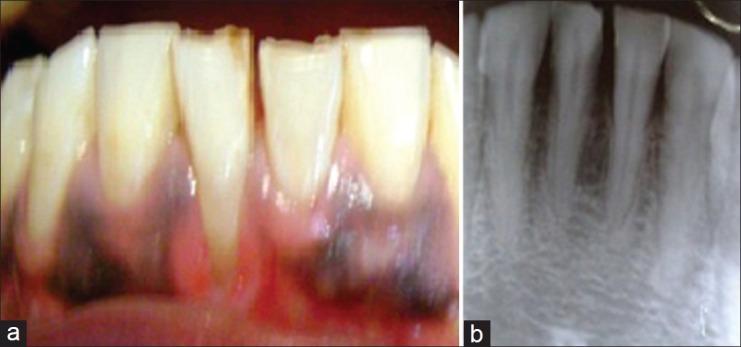

Gingival recession is a common occurrence and patients often report to dental clinic with associated problems such as root surface hypersensitivity, esthetic concerns, cervical root abrasions, and root caries that make it a concern for patients. Based upon the fact that gingival recession is an enigma for clinicians because of multitude of etiological factors and plethora of treatment modalities present for its treatment, a survey was conducted to assess knowledge as well as opinion about most common etiology, classification, and preferred treatment of gingival recession and to evaluate the interest and satisfaction of dentists in practicing periodontics.

牙龈退缩是一种常见情况,患者常因相关问题如牙根面过敏、美观问题、颈部牙根磨损和根龋等前往牙科诊所就诊,这使其成为患者关注的问题。鉴于牙龈退缩因多种病因和大量治疗方式而给临床医生带来难题,开展了一项调查,以评估关于牙龈退缩最常见病因、分类和首选治疗方法的知识及看法,并评估牙医对牙周病学实践的兴趣和满意度。